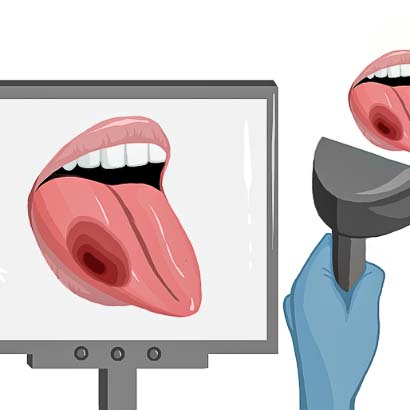

Intraoperative imaging panitumumab-IRDye800 (fluorescence)

Primary tumor prior to resection

Wound bed post re-resection of tumor

Fluorescence imaging of the tumor was performed prior to resection and after resection to “check” the wound bed. In the upper row the tumor is clearly visible with fluorescence and in the bottom row you can see that the wound bed is empty – there is no suspicious fluorescence left. The middle column of tiles show the fluorescence signal in black and white where the “white” represents the tumor and the black the background (= no fluorescence signal). The right column of tiles shows the overlay of the brightfield photo (in greyscale) and the fluorescence (red-yellow-blue heatmap). This image provides anatomical context to the surgeon – the surgeon can see where is the fluorescence located with regard to the tumor area.